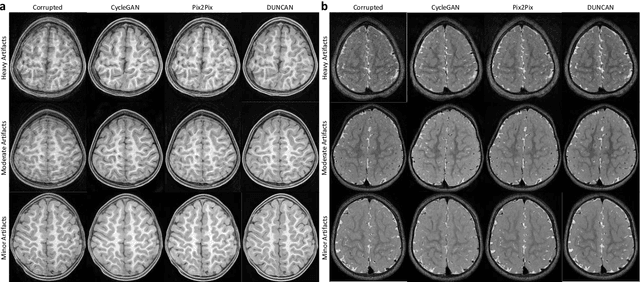

Abstract:Retrospective artifact correction (RAC) improves image quality post acquisition and enhances image usability. Recent machine learning driven techniques for RAC are predominantly based on supervised learning and therefore practical utility can be limited as data with paired artifact-free and artifact-corrupted images are typically insufficient or even non-existent. Here we show that unwanted image artifacts can be disentangled and removed from an image via an RAC neural network learned with unpaired data. This implies that our method does not require matching artifact-corrupted data to be either collected via acquisition or generated via simulation. Experimental results demonstrate that our method is remarkably effective in removing artifacts and retaining anatomical details in images with different contrasts.